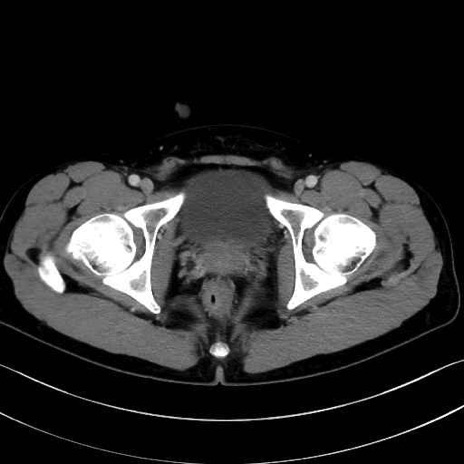

梨状筋(piriformis muscle) のCT画像の解剖

大腿方形筋 (Quadratus femoris)